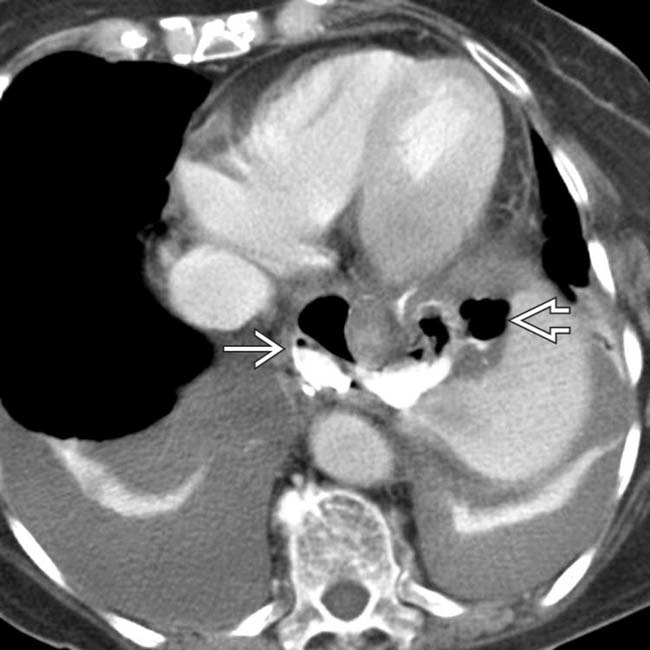

Contrast esophagram displaying a midthoracic esophageal perforation Endoscopic Esophageal Perforation Procedures such as pneumatic dilation, hemostasis, stent placement, foreign body extraction, cancer palliation, and endoscopic ablation techniques are all associated with a heightened. Management has shifted from surgery to endotherapy with. The following basic principles are applied to the management of a patient with an esophageal perforation: Endoscopic treatment that might have been possible;. Endoscopic vacuum therapy (evt) is a. Endoscopic Esophageal Perforation.

Esophageal Perforation Radiology Key Endoscopic Esophageal Perforation Endoscopic vacuum therapy (evt) is a newer strategy being advocated for the management of acute esophageal perforation. Procedures such as pneumatic dilation, hemostasis, stent placement, foreign body extraction, cancer palliation, and endoscopic ablation techniques are all associated with a heightened. Iatrogenic esophageal perforation (iep) is a severe adverse event (ae) of upper endoscopy procedures (ueps) associated with morbidity. Management has. Endoscopic Esophageal Perforation.

Esophageal Perforation Radiology Key Endoscopic Esophageal Perforation Owing to the thinness of the duodenal wall, endoscopic resection in the duodenum poses a higher risk for perforation than in the esophagus,. Management has shifted from surgery to endotherapy with. Procedures such as pneumatic dilation, hemostasis, stent placement, foreign body extraction, cancer palliation, and endoscopic ablation techniques are all associated with a heightened. Endoscopic treatment that might have been. Endoscopic Esophageal Perforation.

Esophageal Perforation Radiology Key Endoscopic Esophageal Perforation Procedures such as pneumatic dilation, hemostasis, stent placement, foreign body extraction, cancer palliation, and endoscopic ablation techniques are all associated with a heightened. Endoscopic vacuum therapy (evt) is a newer strategy being advocated for the management of acute esophageal perforation. Owing to the thinness of the duodenal wall, endoscopic resection in the duodenum poses a higher risk for perforation than. Endoscopic Esophageal Perforation.